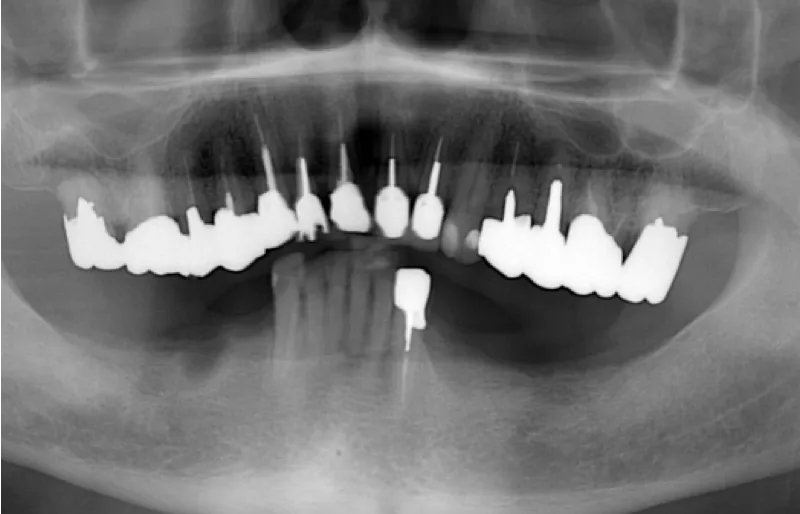

拝見したところ、下の両側の奥歯(第1小臼歯/4番〜第2大臼歯/7番)が欠損しており、前歯でしか物が噛めない状態でした。 取り外し式の入れ歯をご使用されていましたが、違和感があるご様子で、装着すると吐き気が出てしまっていました。

奥歯でしっかりと噛めるようにするために、あごの骨に人工の歯根を埋めて歯を装着する「インプラント治療」をご提案しました。

インプラントの本数については、奥歯で噛んだときの力を分散させるため、左右に3本ずつ埋めることをおすすめしました。

3ヶ月後、インプラントが骨としっかり定着したことを確認してから、左右同時に被せ物を作製し、インプラントの上に取り付けて治療を終了しました。